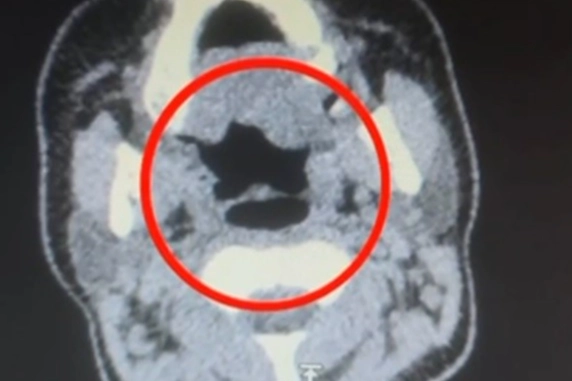

Kayseri İl Emniyet Müdürlüğü Narkotik Suçlarla Mücadele Şube Müdürlüğü ekipleri, uluslararası uyuşturucu madde ticareti yapan kurye şahıslara yönelik operasyon düzenledi. Operasyonda A.R.'yi (27) gözaltına alan ekipler, şahsı hastane muayenesine götürdü. Şüphelinin yapılan iç beden muayenesinde, mide kısmında bulunduğu tespit edilen 50 adet kapsül şeklinde toplam 500 gram uyuşturucu madde ele geçirildi. 'Uyuşturucu madde ticareti yapmak' suçundan gözaltına alınan şüpheli emniyete götürüldü.